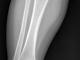

am doing a project on leg bone (Tibia) fracture detection using image processing. I am using digital x-Ray bone fracture images to deal with this project. I was not able to find a proper method to identify bone fractures on above mentioned bone due to the high noise and variations of the fracture types.

and the color of the bone area is not identical each and every image. so its really hard to find a global threshold value for all images. So plzzz suggest me a proper segmenting and fracture detection method to move on this project....

Does anyone have any idea how to handle this project using x-ray bone fracture images??? i have attached an image of that bone.

I assume the first pic is a none fracture and second is the fracture, ok the way I would approach is to apply an edge detect and then apply thresholding, this give you the below image, but I would first re-orientate the image so the leg bone faces in one direct (up - down/ left - right) then you can simple scan along the image and look for deviations from a straight path, as you can see the part with the break will be the only part within the center box that is not more or less and straight line.

This image has prewitt applied and then thresholding... but simply have all input images orientated so the bone is at a straight line and will be easy to implement a function to scan along and look for deviations.